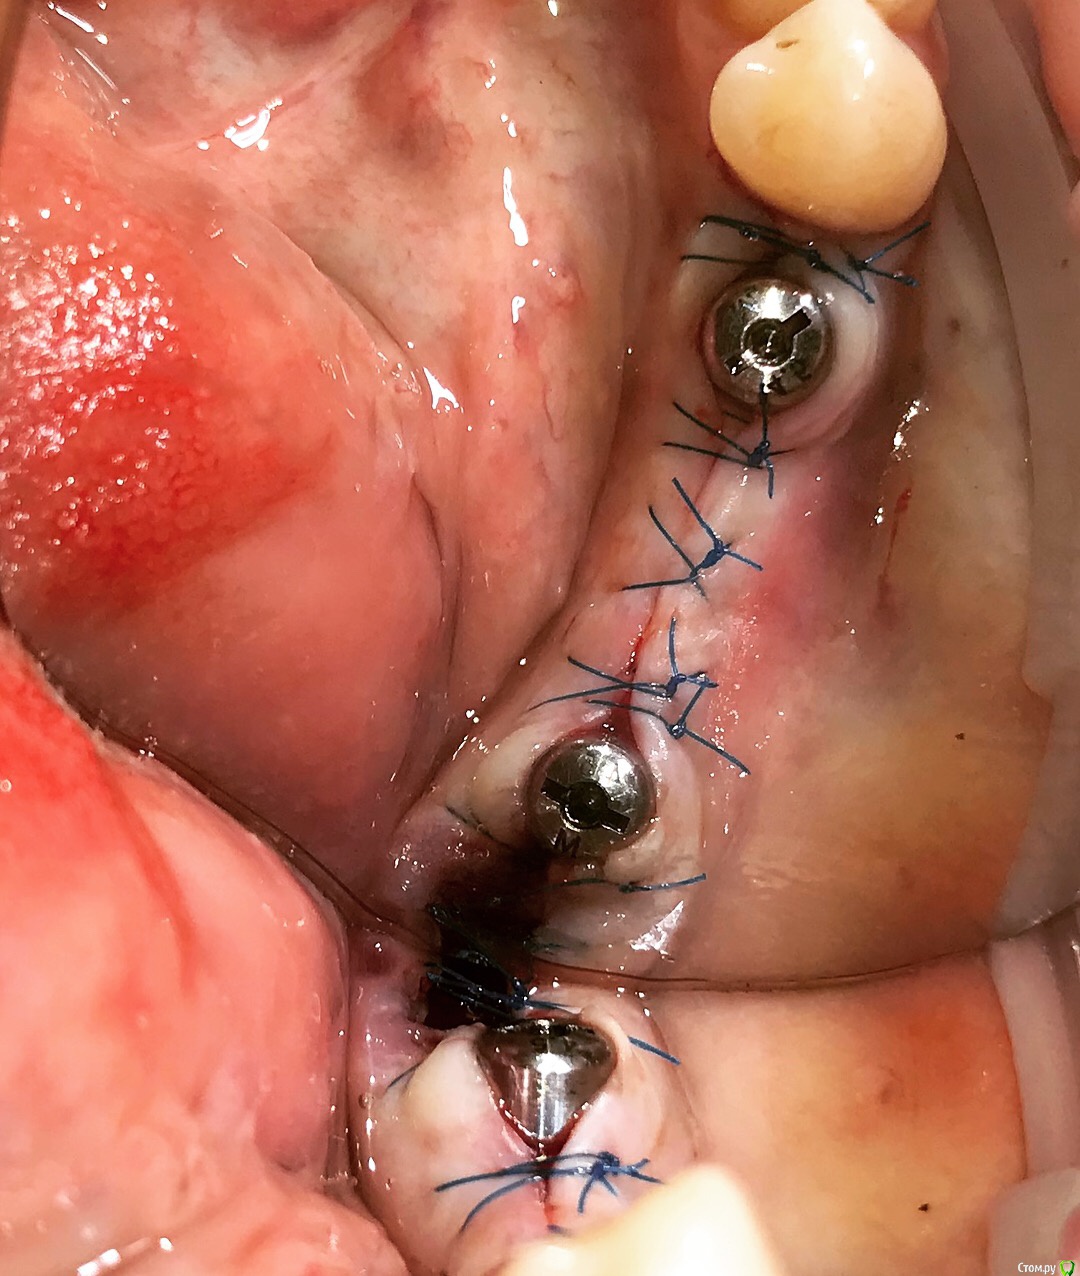

Santi Опубликовано 12 сентября, 2018 Поделиться Опубликовано 12 сентября, 2018 Коллеги, интересно мнение как бы вы поступили в аналогичной ситуации) Имеем Область забора и полученный ССТ Сразу после 2,5 мес пост оп 9 Ссылка на комментарий